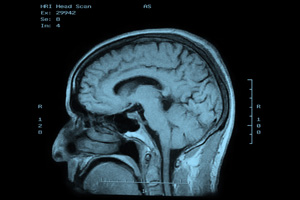

- le Système 1 est émotionnel, rapide, intuitif et fonctionne en mode automatique, sans que nous prenions conscience de son activité ni de son existence.

- Le Système 2 est plus réfléchi, plus calculateur et lent ; il contrôle le Système 1. Système 2 n’est actif que pour réaliser une tâche cognitive bien précise, qui correspond à un certain effort mental.

Bref, les biais cognitifs sont le résultat du fait que nous sommes des « animaux biologiques » au cerveau complexe et qui réagit à des stimuli qui l’influencent sans que nous ne nous en apercevions.